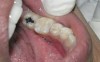

The search for an ideal direct esthetic restorative material is still ongoing. Among the array of RBC materials, some are readily available in the market (flowable, packable, and fiber-reinforced), others have just recently been introduced (siloranes-based), and a few are still in development phase (fluoride-releasing). Individual properties of different RBC materials define their advantages, disadvantages, and clinical uses. Each type of RBC material has its own virtues in some clinical aspects and shortcomings in other aspects. Every material possesses either one or the other ideal properties of a restorative material, but not all of them. Therefore, it is important for a clinician to use every material judiciously and for a clinical application for which it is best suited (Figure 5, Figure 6, Figure 7, Figure 8, Figure 9 and Figure 10).

Figure 5  Clinical applications of RBCs for posterior restorations: occlusal caries restored with silorane-based RBC

Figure 5